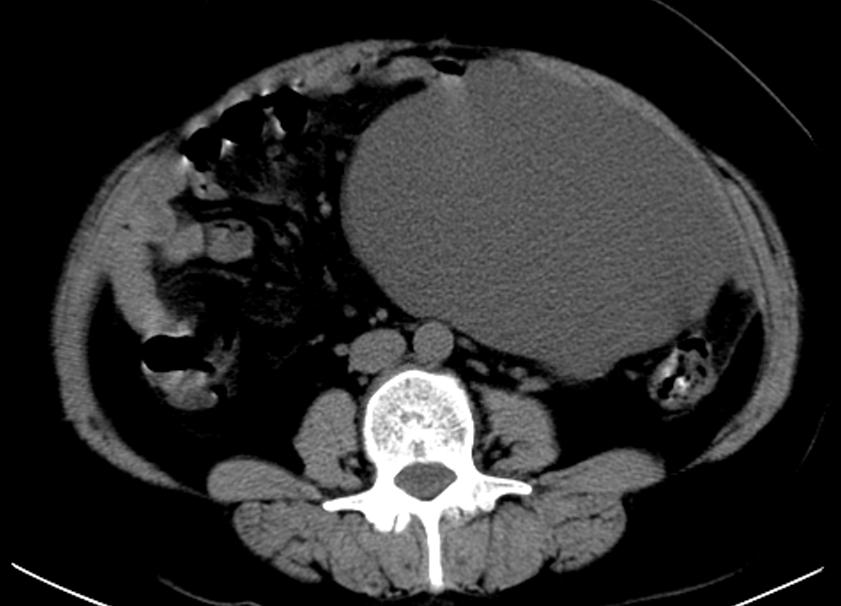

③胸腹部CT(2020.10.27 本院)示:右肺中叶小结节(伴少许钙化);下腹部巨大囊性占位并腹膜结节及絮状改变。

④盆腔MRI(2020.10.28 本院)示:腹盆腔囊实性占位(实性部分及分隔可见强化,部分囊性灶积血可能),考虑囊腺Ca可能性大,建议结合临床及综合病检。 盆腔多发稍大淋巴结,建议结合临床。子宫前壁囊性灶;子宫信号稍欠均匀;建议相关专科检查。 腹盆腔内积液。腹盆腔部分系膜间隙稍浑浊。